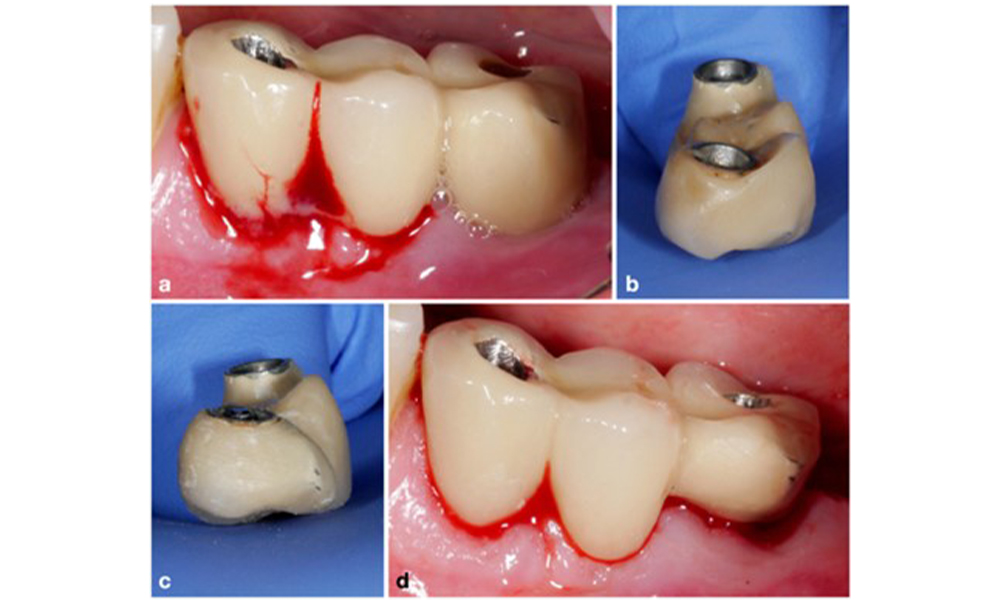

Der primäre ätiologische Faktor für periimplantäre biologische Komplikationen ist der orale Biofilm. Daher sollten bei der Behandlung in jedem Fall zwei wesentliche Aspekte berücksichtigt werden, unabhängig von einer Diagnose periimplantärer Mukositis oder Periimplantitis: (1) die Qualität der Oralhygiene und (2) die Reinigungsfreundlichkeit der prothetischen Restauration (Abb. 4).

In diesem Sinne sollten sowohl die tägliche Oralhygiene des Patienten als auch die Gestaltung der prothetischen Restauration sowie die Positionierung des Implantats eine wirkungsvolle Reinigung unterstützen. Bei Bedarf sind Anpassungen der vorhandenen Restauration (Abb. 5) und konkrete Anweisungen für eine maßgeschneiderte Oralhygiene von größter Bedeutung (Abb. 6) (Hamilton et al. 2023; Jepsen et al. 2015).